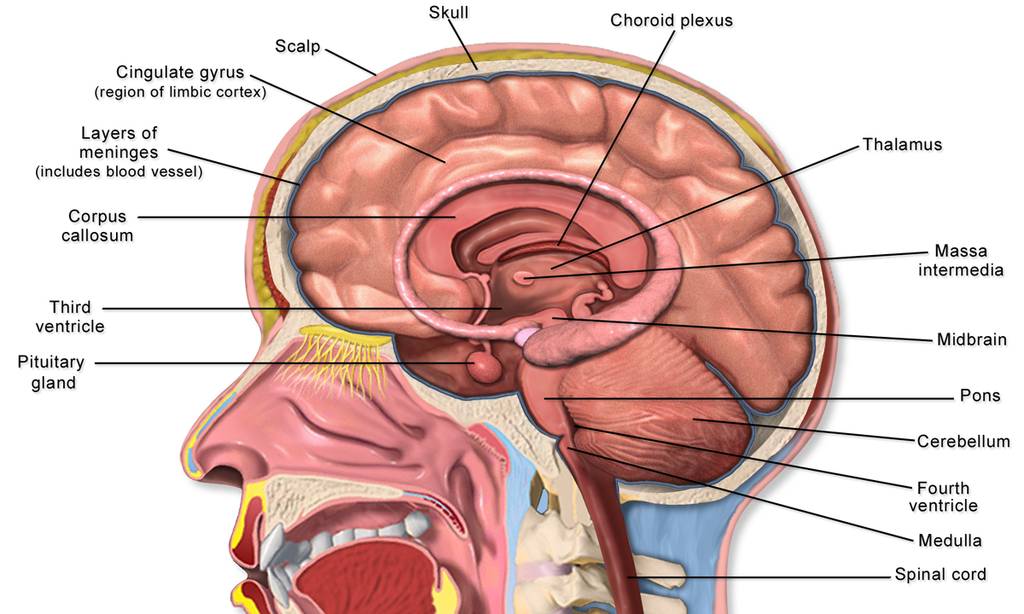

Anatomy of the brain

Fig. 1.

The most rough division is: the hindbrain, midbrain, and forebrain. In Latin this will be: rhombencephalon, mesencephalon, and prosencephalon. Going in down-top direction, rhombencephalon is further subdivided into myelencephalon and metencephalon and prosencephalon – into diencephalon (the intermediate brain) and telencephalon. Latin terms sound terribly, but fortunately they may be encountered mainly in very specialized literature. Myelencephalon is also called medulla oblongata (the oblong brain).

Another often term is the brain stem. It begins from the spinal cord and includes medulla oblongata, pons of the hindbrain, the midbrain, and sometimes diencephalon too.